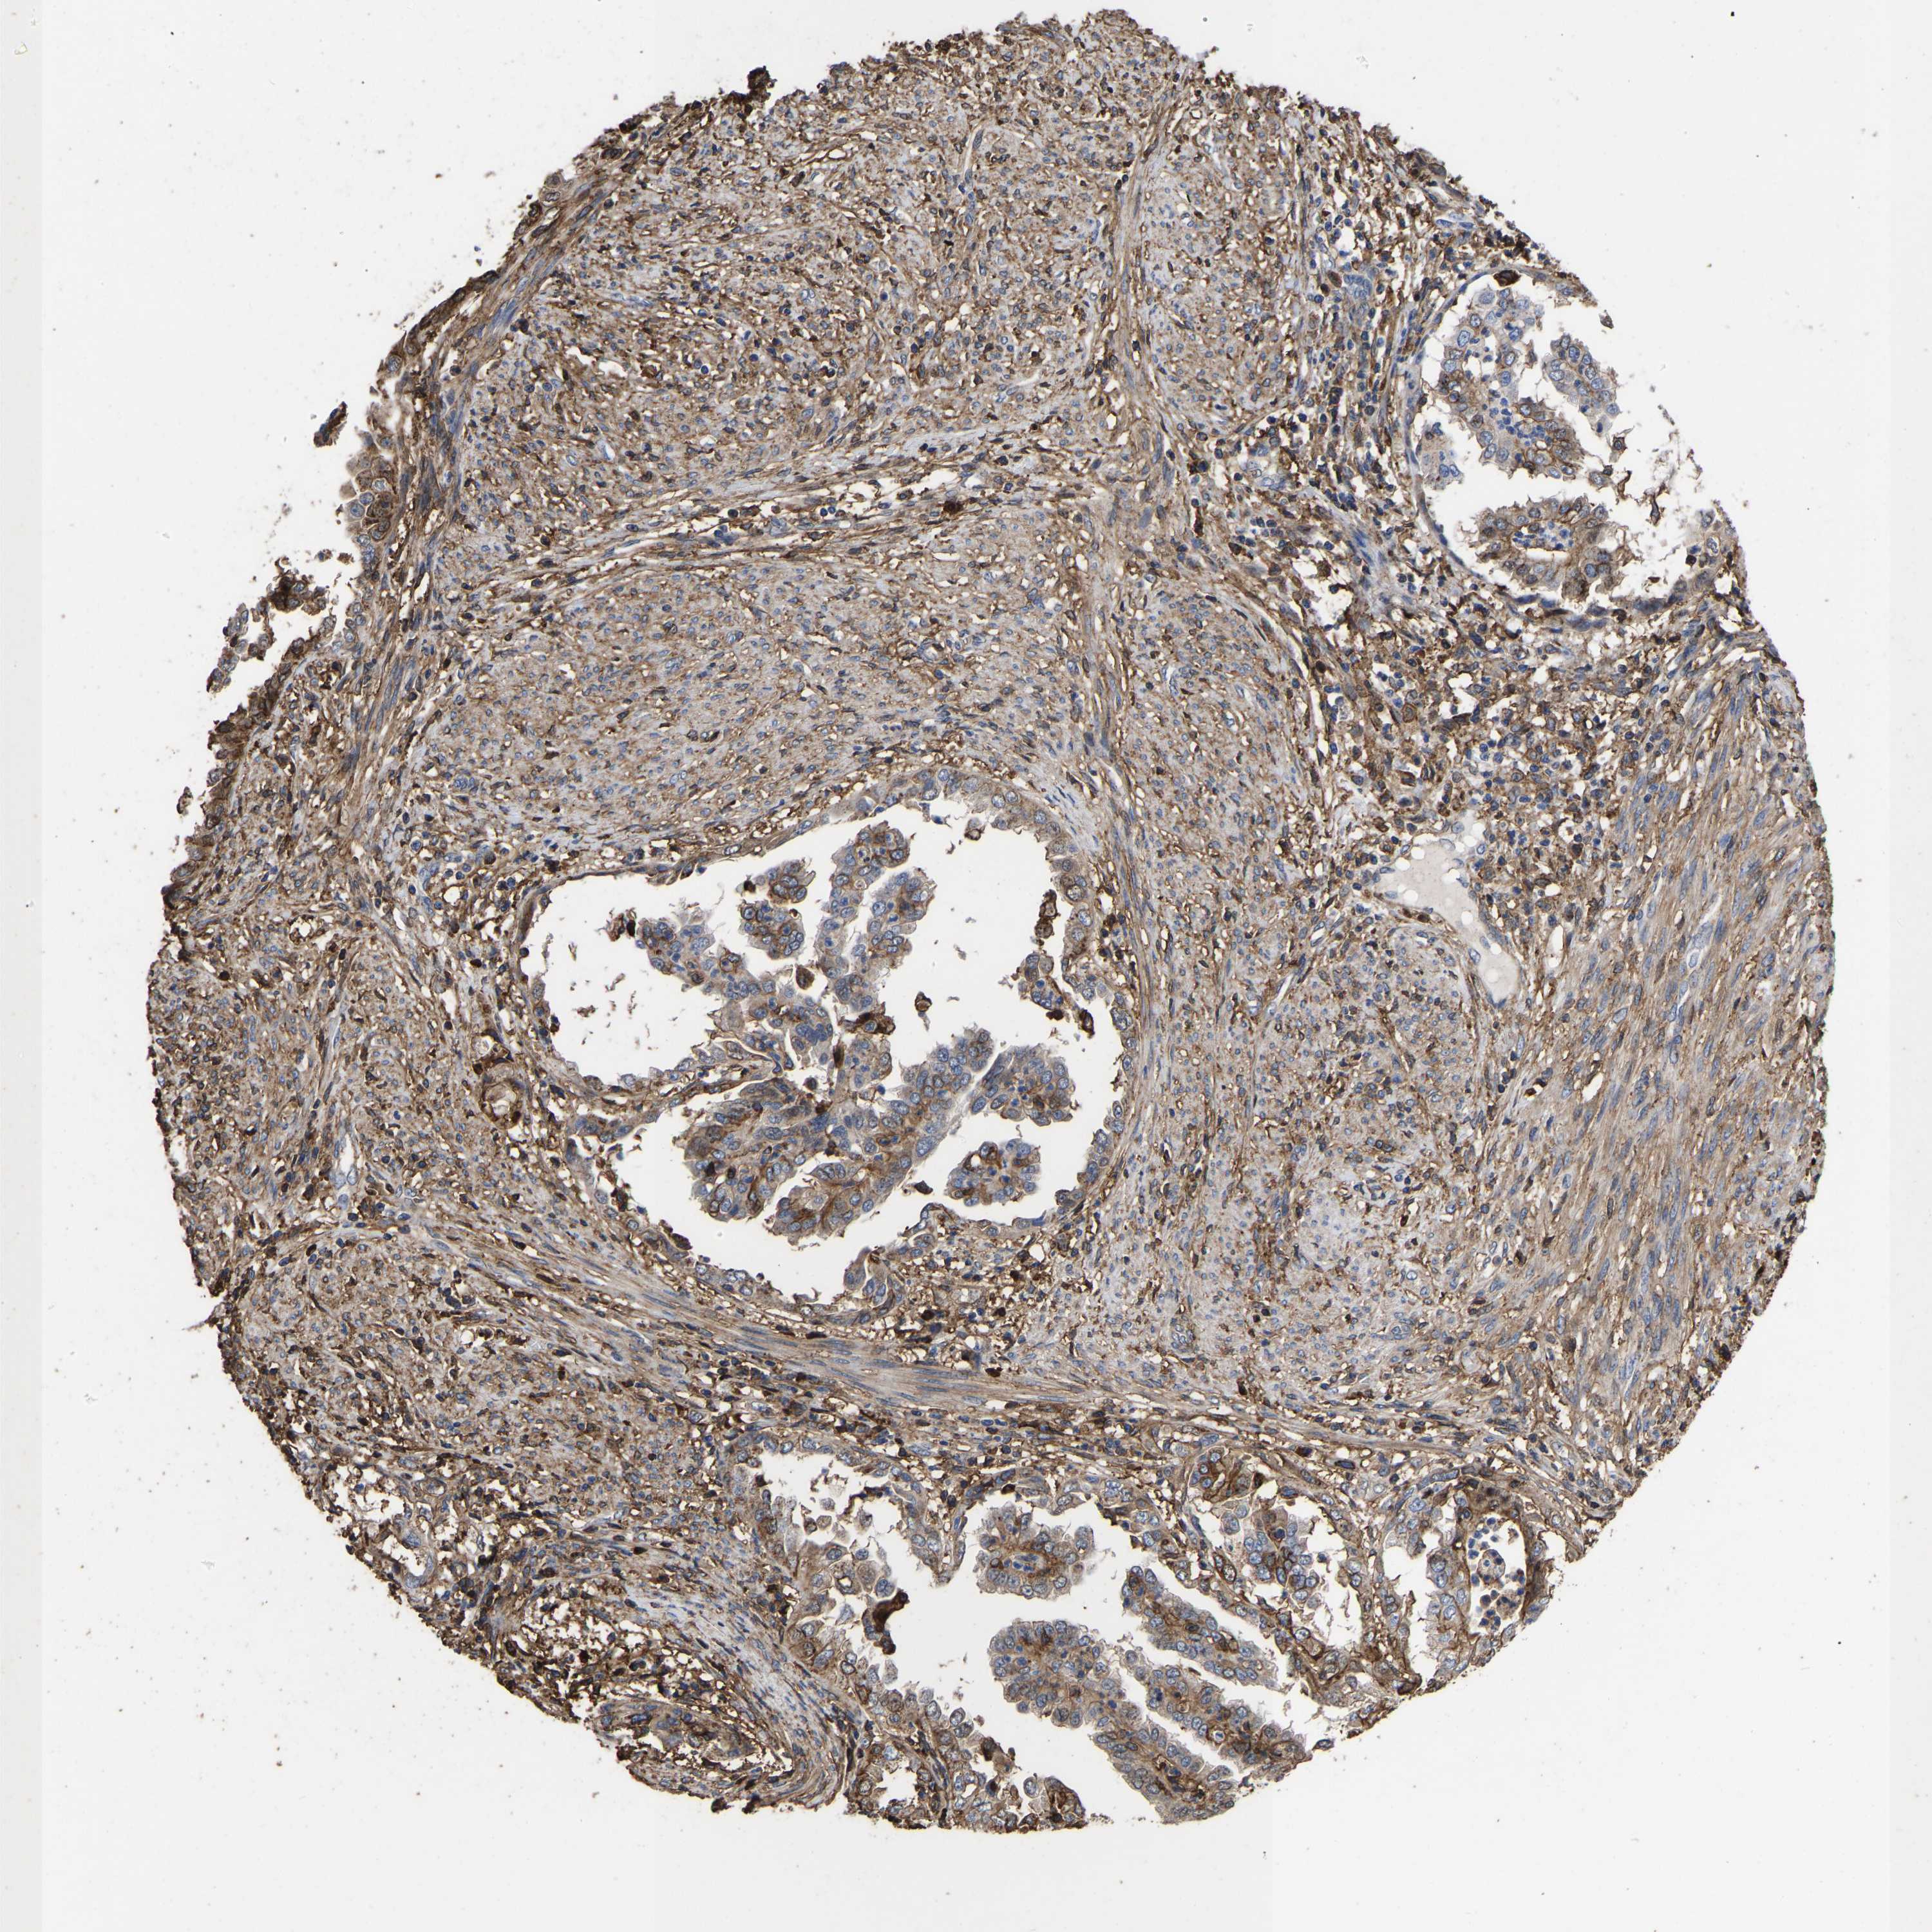

ENDOMETRIAL CANCER - Protein expressioni

A mouse-over function shows sample information and annotation data. Click on an image to view it in a full screen mode. Samples can be filtered based on level of antibody staining by selecting one or several of the following categories: high, medium, low and not detected. The assay and annotation is described here.

Note that samples used for immunohistochemistry by the Human Protein Atlas do not correspond to samples in the TCGA dataset.

Antibody stainingi

Antibody staining in the annotated cell types in the current human tissue is reported as not detected, low, medium, or high, based on conventional immunohistochemistry profiling in selected tissues. This score is based on the combination of the staining intensity and fraction of stained cells.

Each image is clickable and will lead to virtual microscopy that enables deeper exploration of all samples and also displays staining intensity scores, fraction scores and subcellular localization as well as patient and tissue information for each sample.

Antibody HPA018844

Staining

High

Medium

Low

Not detected

Intensity

Strong

Moderate

Weak

Negative

Quantity

>75%

75%-25%

<25%

None

Location

Nuclear

Cytoplasmic/membranous

Cytoplasmic/membranous,nuclear

Adenocarcinoma, NOS

Adenoma, NOS